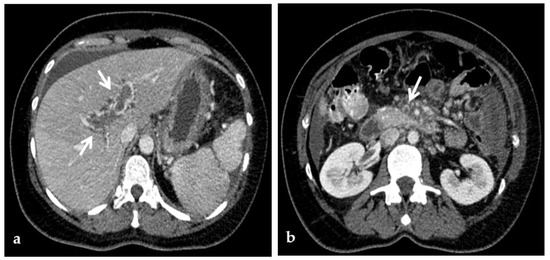

Figure 4.

CT images of portal vein thrombosis in a 62-year-old male affected by myelofibrosis, who presented with intense abdominal pain. (a) Portal phase axial CT image shows a lack of luminal enhancement in the porta hepatis, increased portal vein caliber with enhancing walls, and a low-attenuating thrombus within the lumen, consistent with acute portal vein thrombosis (white arrow). Multiple collateral vessels forming a cavernoma are seen at the hepatic hilum (black arrow). (b) Portal phase coronal CT image better shows the extension of portal vein thrombosis, also involving the splenic vein (arrow).

In the chronic form, the thrombosed vessel can be hypodense, containing linear calcifications, obliterated or shrunk, with cavernous transformation [39,58]. In candidates for LT, calcifications in the portal vein should be actively investigated, because they indicate a more fragile vessel and can hinder surgical anastomoses creation [58]. Splenomegaly and splenic artery aneurysms are also relevant findings readily depicted by CT (Figure 5).